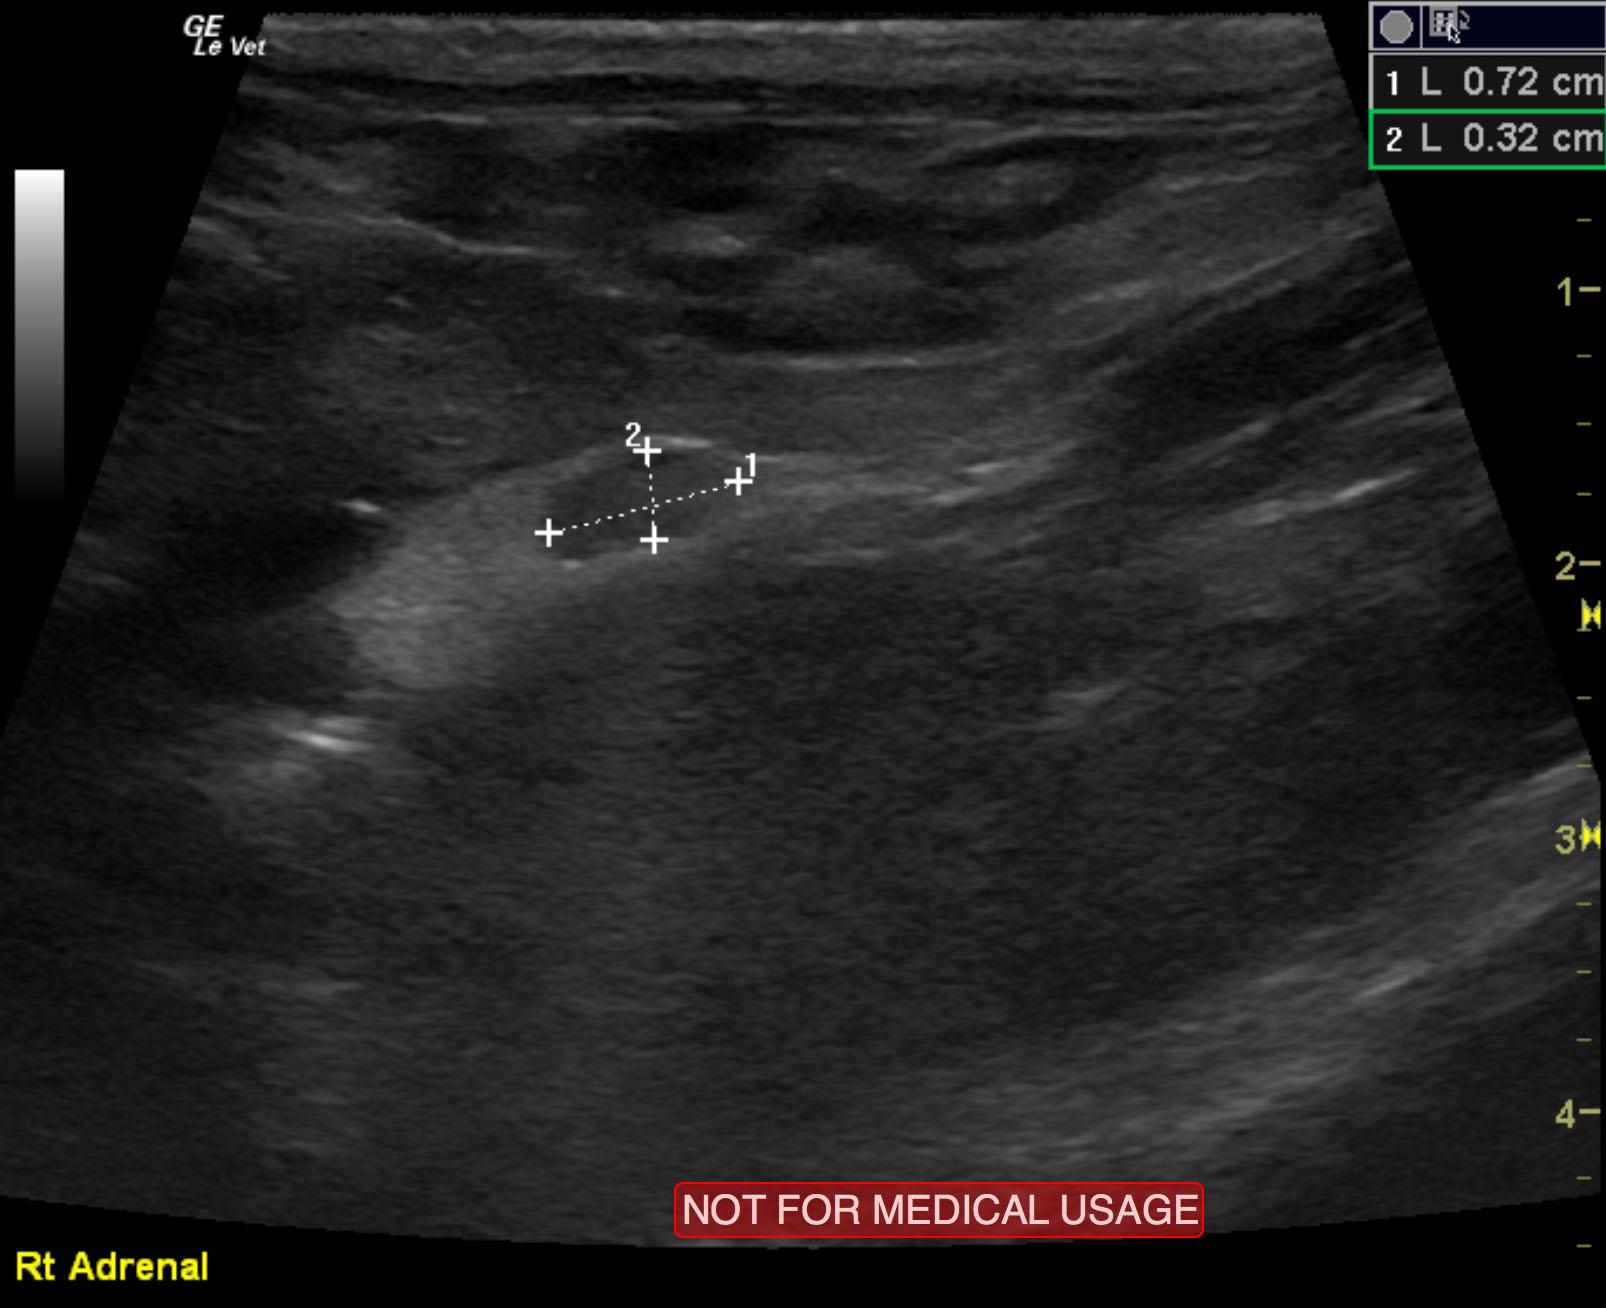

The left adrenal gland comprised a mass that measured 2.2 x 1.12 cm. Capsular expansion was noted at the caudal pole with pericapsular inflammatory pattern. It appeared significantly vascular with a trace amount of free fluid noted adjacent to it. This suggests a fairly aggressive process, but there was no evidence of vascular invasion noted. The right adrenal gland was uniform and measured 0.72 x 0.32 cm. Lymph node enlargement was noted in the epigastric region and measured 1.02 x 0.82 cm. A separate lymph node medial to the spleen was also enlarged, measuring 1 x 0.82 cm.